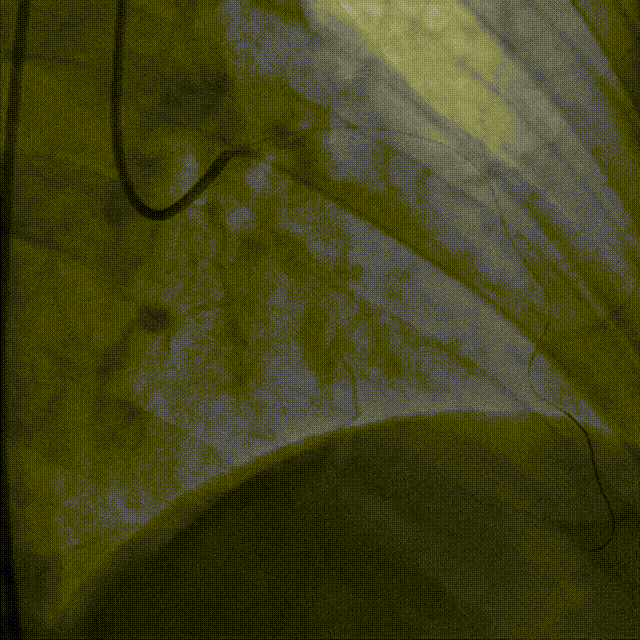

谷兴华教授 山东大学齐鲁医院 锚定终身获益,重视首次干预选择:心脏瓣膜病介入中心成立2年多来,中心核心目标始终保证在解决即刻病症的基础上,护航患者的全生命周期健康管理。 摆在眼前的实际是日益年轻化的患者群体,这意味着我们从手术伊始,就必须将患者未来数十年的生活质量和再次干预风险纳入核心考量,主动规划长远的健康路径。此次患者选择更具耐久的新型干瓣技术,力求减少患者未来再次干预的风险。同时,通过“TAVR+PCI一站式手术”这样的团队协作模式,系统性地处理多重心血管问题,避免分次手术的负担与风险,这正是我们中心一直秉持的“心脏瓣膜病全生命周期管理”理念的实践。让我们一起探索从“治已病”真正迈向“管长远”,让更多的患者获益! 病例特点速览 本次救治的患者,病情呈现“基础病交织、多病变叠加、锚定风险高”三大核心特征。患者为65岁,女性,病变特点TypeI型二叶瓣、轻度钙化,锚定风险大;同时患有冠状动脉粥样硬化性心脏病、慢阻肺(COPD);既往有长期吸烟饮酒史、脑梗死病史、高血压病史、乙肝小三阳病史及腹股沟疝修补手术史,患者STS评分9.32%,外科手术高危,经齐鲁医院瓣膜中心团队评估认为:局麻下“一站式TAVR+PCI”为最优治疗方案,结合患者较年轻,可选择具有长期耐久性的干瓣。 患者病史 主诉:活动后胸闷、憋喘余,加重20余天 既往史:30年前确诊乙肝小三阳,否认其他传染病史;有右腹股沟疝修补手术史,高血压病史,近期规律服药控制。 现病史:患者1年前出现活动后胸闷、憋喘,休息可缓解,为进一步诊治。2月前因“突发意识模糊、口齿不清”于当地医院入院,诊断为“急性脑梗死”,予以微创介入取栓治疗,恢复可,未遗留后遗症。20天前于当地医院再次入院行脑血管支架植入术,术后出现胸闷、憋喘,伴大汗,行心脏超声提示主动脉瓣重度狭窄,并行冠脉造影检查,予以药物治疗。10天前就诊于我院复查心脏超声提示二叶式主动脉瓣,主动脉瓣狭窄(重度)并反流(轻度)。患者现仍感胸闷,双上臂疼痛不适,咳嗽咳痰,日常活动受限。为行进一步治疗就诊于我院,门诊以“主动脉瓣狭窄、冠状动脉粥样硬化性心脏病”收入院; 个人史:吸烟50年,饮酒50年; 体格检查:体温:36℃,脉搏:67次/分,呼吸:18次/分,血压:143/76mmHg; 术前超声提示: 二叶式主动脉瓣主动脉瓣狭窄(重度)并反流(轻度);升主动脉扩张、左心扩大三尖瓣反流(少量);左室充盈异常;CW测最大压差86mmHg,平均压差43mmHg,最大血流速度463cm/s,连续方程法估测主动脉瓣口面积0.78cm² 术前CT评估 Type1型二叶瓣,轻度钙化、左右融合,主动脉瓣环径25.3mm,LVOT直径25.5mm,鱼嘴空间约26.6mm,主要靠瓣环锚定。窦部空间大、左右融合,VTC空间足够,无冠脉风险 ;左室内径正常,主动脉瓣环水平夹角49.6°。外周双侧入路内径可,髂外动脉存在散在钙化、双侧入路能够支持20F大鞘通过,右股低分叉,主动脉弓距弓角可。 个性化手术策略:局麻一站式方案+创新瓣膜精准适配 入路选择:主入路:右侧股动脉(右股分叉上方1cm处穿刺);辅入路:左侧股动脉;器械:20F大鞘; 手术流程规划:局麻下行同期一站式TAVR+PCI,植入ProStyle A®预装干瓣; 瓣膜选型与预处理:瓣膜型号:ProStyle A® AV32;不预扩; 定位与释放方案:初始定位:瓣上3mm处释放,瓣膜自然下滑至工作位,最终目标“0-瓣下5mm位”。 手术过程:局麻一站式操作+创新瓣膜植入,无缝衔接 手术团队按预设方案稳步推进,实现TAVR、PCI与ProStyle A®干瓣植入的无缝衔接: 1.术前准备:完成影像评估、血管通路建立,确认ProStyle A® AV32瓣膜状态; 2.PCI治疗:通过主入路完成左冠造影,前降支、对角支明显狭窄,精准植入两枚支架,恢复冠脉血供; 左冠造影,前降支、对角支病变 PCI后造影,病变血管充盈良好 3.主动脉根部造影:确认主动脉根部解剖结构,并精准跨瓣; 主动脉根部造影 精准跨瓣 4.干瓣植入:将瓣膜输送过弓、过瓣,并精准定位; 输送系统柔顺过弓 精准定位 5.术中评估:释放瓣膜至工作状态,再次造影评估,位置满意,完全释放瓣膜; 工作位评估 32号瓣膜稳定脱钩 6.释放后造影:可见瓣膜位置满意、形态良好,无明显瓣周漏。 最终造影,位置形态良好,无瓣周漏 术后超声探查:位置(瓣下4mm)、形态良好,无瓣周漏,PGmean=10mmHg。 此次手术的成功,体现了山东大学齐鲁医院心脏瓣膜病介入中心秉承的“心脏瓣膜病全生命周期管理”的理念和团队协作的临床能力。面对低龄高风险复杂病例,团队通过术前充分评估、术中精细操作,结合具有长期耐久性的干瓣技术,以一站式方案改善患者症状、提高生活质量并延长寿命,为类似病例的诊疗提供宝贵经验。 专家简介 谷兴华 山东大学齐鲁医院(点击查看专家详细简历)